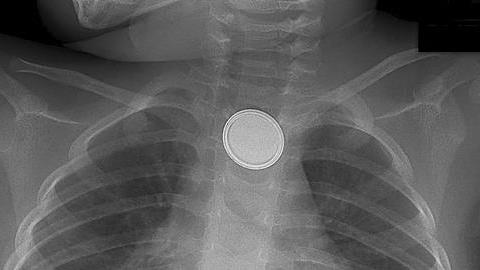

Δακρυσμένος αλλά αξιοπρεπής και δυνατός, αυτός ο μπαμπάς περιγράφει πώς ένα καθημερινό, απλό αντικείμενο που βρίσκεται σε κάθε σπίτι, στέρησε τη ζωή του παιδιού του.